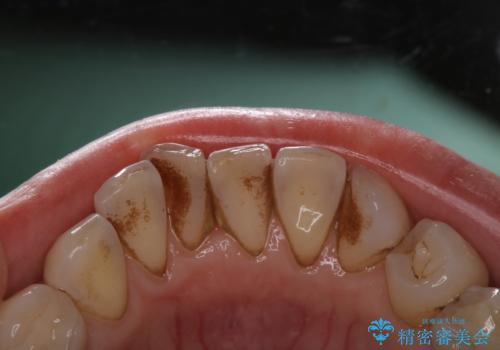

1年ぶりにコーヒーによる着色落とし PMTC